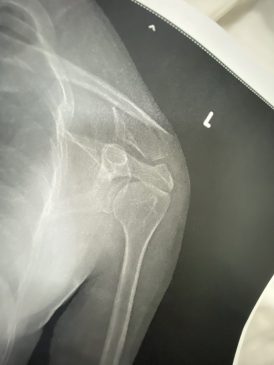

กระทั่งเที่ยวเสร็จ น้องตนกับแหนต่างชาติกลับก่อน จากนั้นตนได้เดินออกมาส่งเพื่อนชาวต่างชาติกลับโรงแรม โดยถือขวดสุราออกมาด้วย และได้ไลฟ์สดขณะยืนอยู่บริเวณฟุตบาทสุขุมวิท 11/1 จู่ ๆ สาวประเภทสองคนเดิมได้เข้ามากระชากศีรษะและทำร้ายร่างกายตนอย่างรุนแรงหลังเกิดเหตุ ผู้เสียหายเข้ารับการรักษาที่โรงพยาบาลตำรวจ แพทย์ตรวจพบว่ากระดูกไหปลาร้าซ้ายหัก และซี่โครงด้านซ้ายหัก3ซี่ ก่อนเข้าแจ้งความร้องทุกข์ที่สถานีตำรวจนครบาลลุมพินี